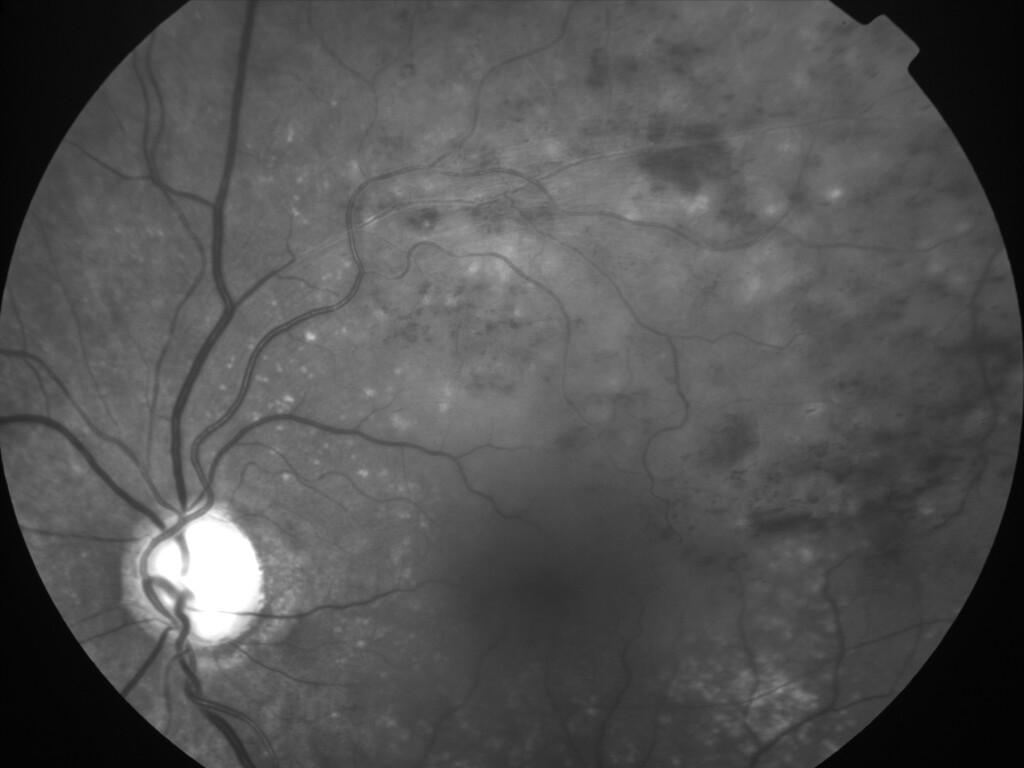

OCCLUSION DE BRANCHE DE LA VTS DE FORME ISCHEMIQUE MAJEURE